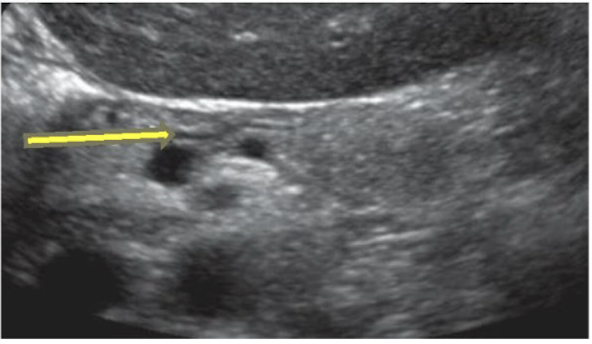

What are the yellow arrows pointing to?

Posterior wall of stomach (BE CAREFUL not to confuse with MPD)